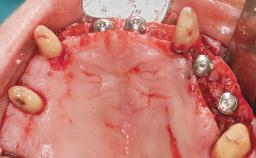

Conventional Loading of Eight Implants in the Maxilla and Final Restoration with a Full-Arch Gold-Ceramic FDP

A 35-year-old Caucasian female presenting with advanced periodontal disease involving both the maxillary and the mandibular dentition was referred for evaluation. The patient, a non-smoker in good general health, requested treatment for recurrent periodontal abscesses, tooth mobility, and discomfort during chewing, as well as restoration of her missing teeth with a fixed prosthesis to improve mastication and esthetics. All residual maxillary teeth exhibited plaque deposits, deep pockets, bleeding on probing, and class III mobility and were evaluated as hopeless. All residual mandibular teeth except tooth 37 could be maintained after periodontal therapy.

Bone Augmentation Horizontal|Staged|Vertical

Augmentation Materials Autogenous block(s)